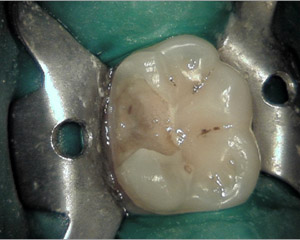

Normalment, amb la exploració clínica s'aprecien molts signes de malalties del pacient: càries, inflamació de genives, sagnat de genives, leucoplàsies, ulceracions, etcètera. Tot així, hi han moltes vegades que el diagnóstic no es pot realitzar, o aquest pot ser erroni si no es realitzen les proves complementàries adients. Al nostre centre disposem de potents càmeres intraorals que ens permeten identificar petites lesions de les dents (fisures, fractures, etc) que d'altre manera passarien desapercebudes.

caries1 caries2 caries3 caries4